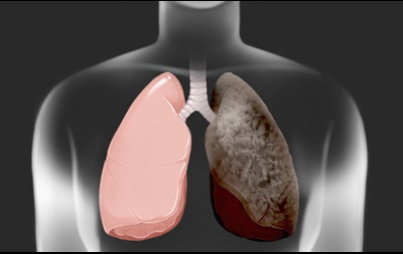

흡연을 하지 않아도 폐암을 취하는 경우가 있습니다만, 이러한 상황을 막기 위한 방법중의 하나, 우선 요리를 할 때는, 연기가 나는 음식을 할경우 실내에서 조리를 할때 환기를 하고 공기를 순환시키는것이 중요 합니다 . 그리고 조리 하는방법으로는 굽거나 튀기는 것보다 쪄서 조리하는 것이 좋습니다 . 그리고 구울 때 탄음식이 되지 않도록 조심해주세요 . 음식이 타면 발생하는 유해 물질이 있지만, 그것을 흡입한다면 폐암의 원인이 될 수 있습니다 .